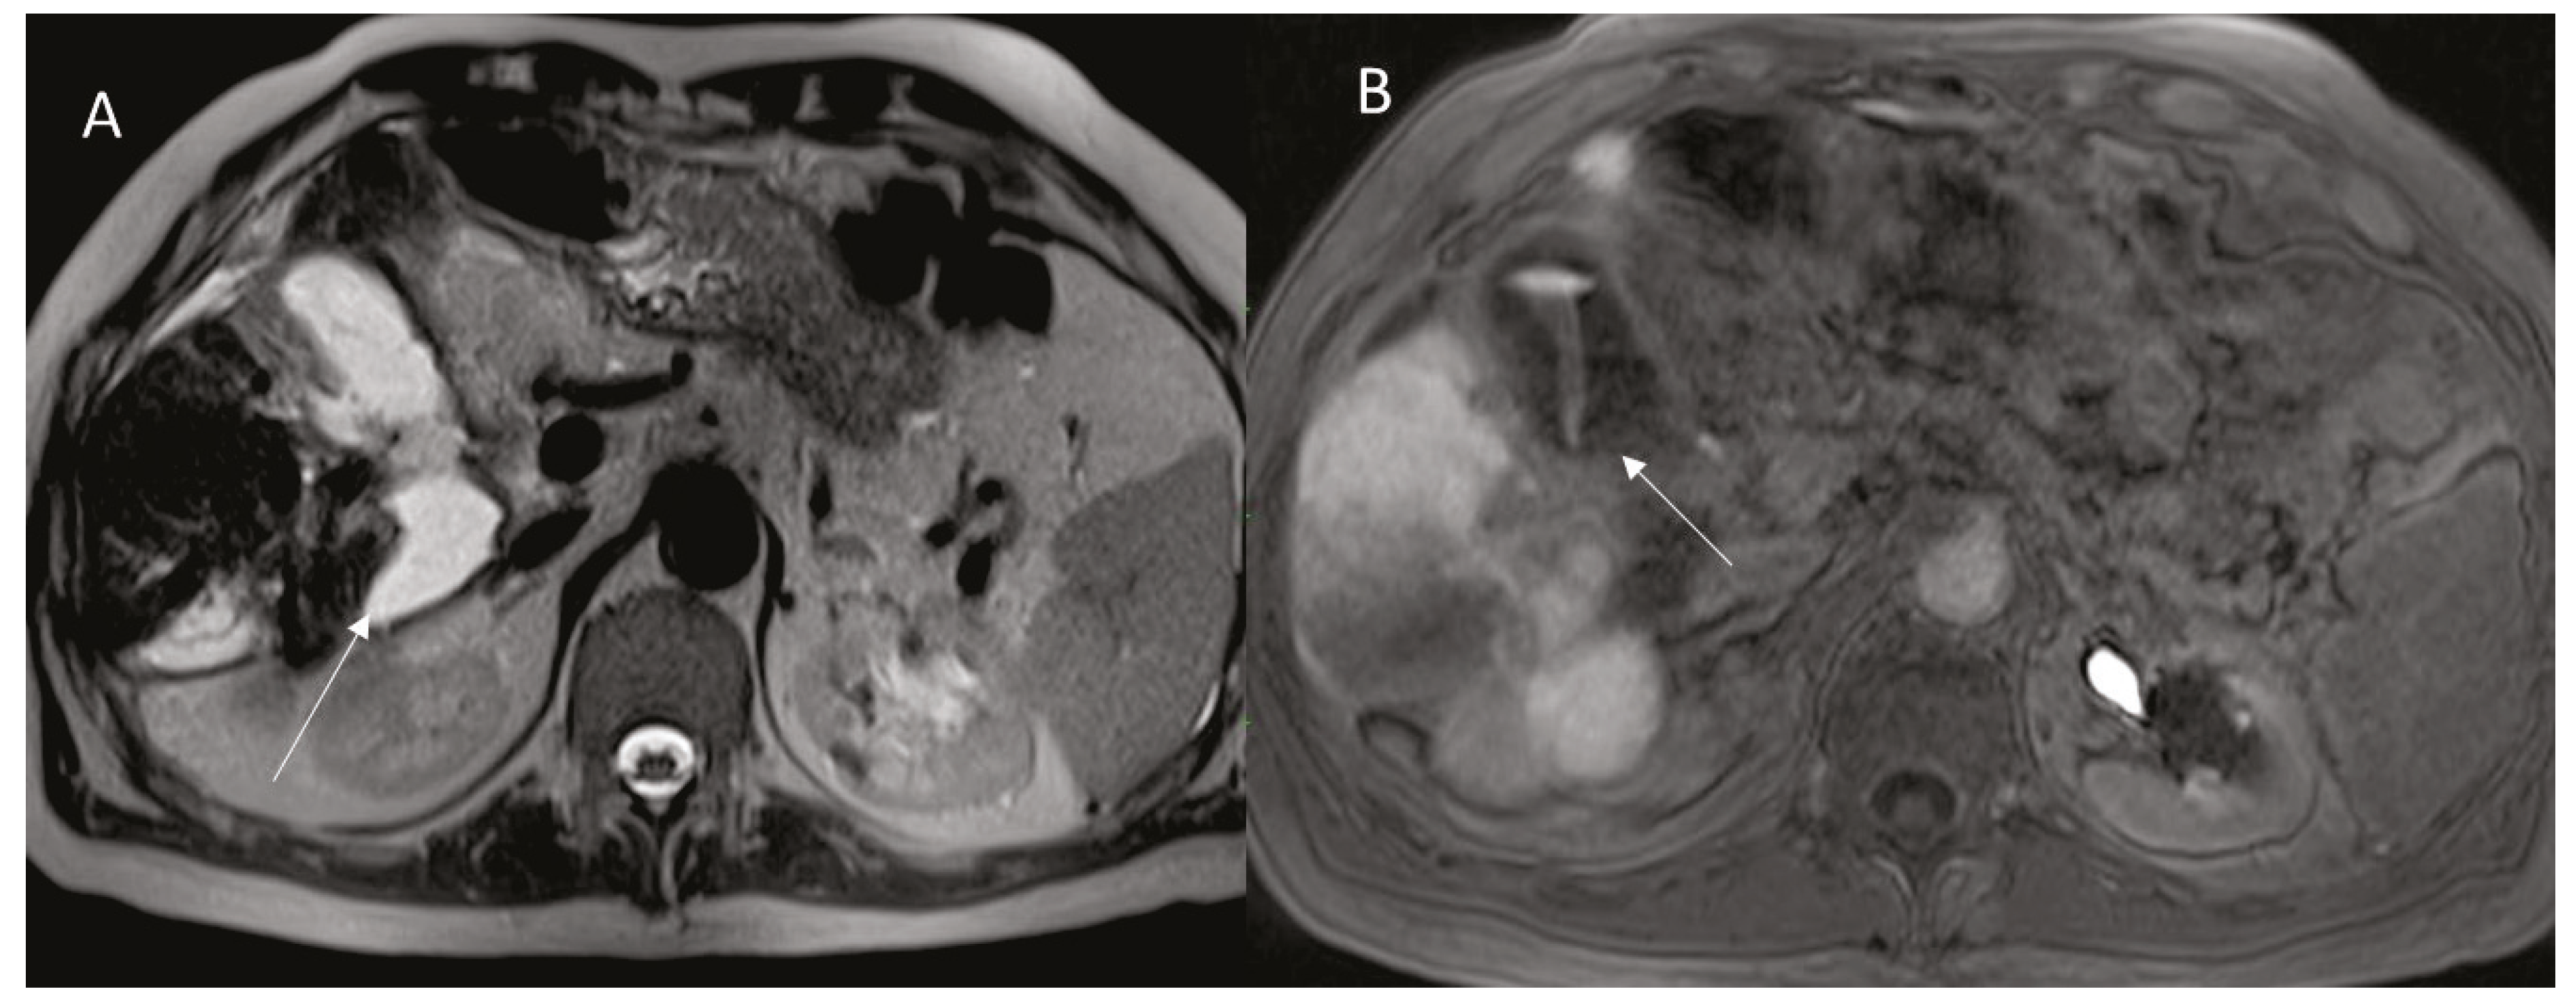

Figure 3. The same patient of Figure 2, MRI assessment ((A): HASTE T2-W sequence, (B): EOB-Phase of contrast study) after 2-month, arrow shows biloma.

However, biliary ducts necrosis due to the pre-stenotic dilatation may lead to the leakage of bile, collecting in intrahepatic (Figure 3) or extrahepatic biloma.

The knowledge of post ablation complications radiological findings can be helpful to detect immediately the main complications that can arise after an ablative procedure, allowing the possibility of early and specific treatment. CT with multiphase contrast study remains the tool to choose in emergency setting, while CEUS is the diagnostic tool that could be used during treatment and as a surveillance tool. MRI with hepatospecific contrast could be used in selected cases (as biliary leak).